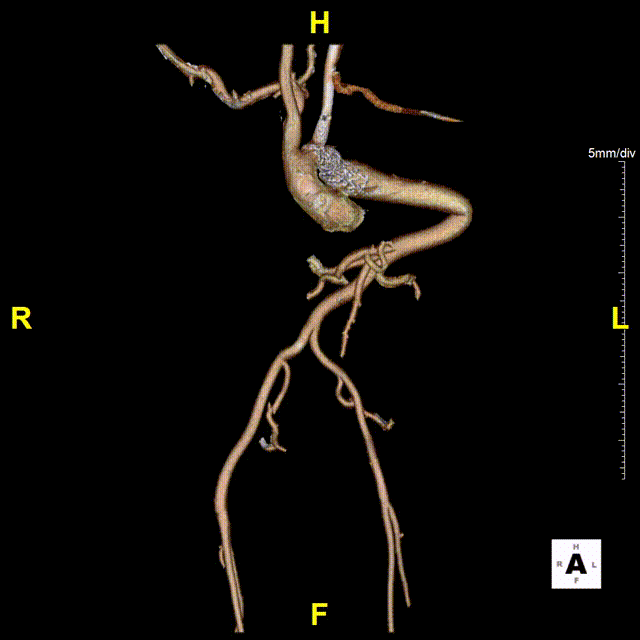

入院后完善进一步检查后发现患者主动脉病变复杂程度远远超过预期。术前检查显示患者左锁骨下动脉瘤最大直径达73.3mm,伴局限性夹层形成,目前瘤体已压迫喉返神经出现声音嘶哑症状,远期发生破裂猝死风险极高。同时,左锁骨下动脉开口近端合并主动脉缩窄,最狭窄处直径仅约10mm。更加雪上加霜的是该患者左椎动脉刚好单独起自主动脉弓狭窄处,且为左椎优势(图1)。结合患者脊柱侧弯畸形病史,进一步查体发现患者存在外耳道、四肢关节等多处畸形,完善基因检测后考虑诊断为Larsen综合征。鉴于患者病史、解剖和主动脉病变的复杂性,开放手术无法充分显露左锁骨下动脉瘤体,更加无法切除瘤体并重建左锁骨下动脉,且开放手术创伤和风险极大。而由于患者主动脉走行扭曲,介入手术存在支架无法输送至目标位置而失败的风险,且腔内重建椎动脉困难,一旦发生内漏,所有努力都将付诸东流。

图1 术前CTA

术后患者安返重症监护室,术后6h患者苏醒并顺利拔出气管插管,第二天转回普通病房。患者术后恢复顺利,复查夹层动脉瘤CTA示主动脉支架位置准确,形态良好,弓上各分支血管血流通畅,左锁骨下动脉瘤隔绝良好,无内漏发生,术后第4天顺利出院。

gore医疗怎么样「胸有乾坤」国际首例 微创杂交技术治疗巨大左锁骨下动脉瘤合并主动脉缩窄Larsen综合症患者_https://www.jmylbn.com_新闻资讯_第15张

术后复查3D图